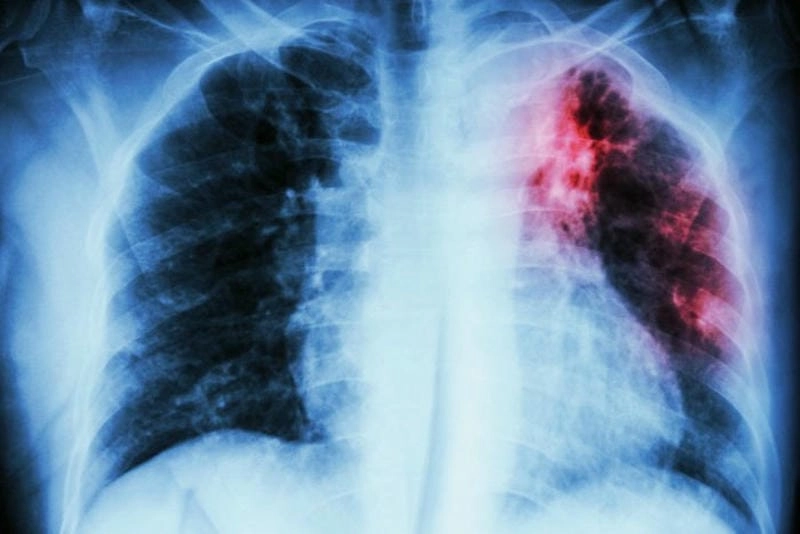

Cảnh báo: tổng hợp ảnh bệnh lao phổi chân thực này không dành cho người yếu tim. Đây là loạt hình ảnh y khoa được các chuyên gia sưu tầm và xác thực, ghi lại quá trình tiến triển của bệnh từ giai đoạn đầu đến giai đoạn nguy kịch. Từng mảng mô phổi bị ăn mòn, xơ hóa, hoại tử được phơi bày rõ nét dưới ánh sáng X-quang lạnh lùng. Những hình ảnh này không chỉ mang tính chất minh họa y học, mà còn là hồi chuông cảnh tỉnh cho bất kỳ ai còn lơ là với căn bệnh nguy hiểm này.

Phân tích chuyên sâu hình ảnh ct lao phổi lâm sàng